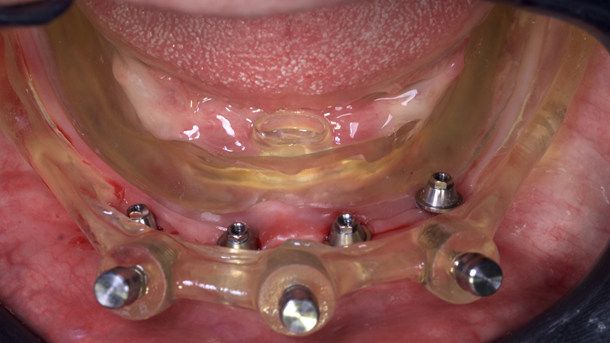

Os arquivos foram enviados para a empresa Raio 3D (Porto Velho – RO) para criação de uma guia empilhável; consistia em três partes que são mencionadas na discussão; e impressão da prótese provisória em resina através do processo de estereolitografia. A base da guia tomográfica e personalizada foi comparada e o exame clínico não mostrou sinais de desalinhamento ou pressão em qualquer área.

O guia foi fixado após estabilização em oclusão com a prótese superior. Após a retirada do guia de oclusão, foi fixada a guia de fresagem e instalação dos implantes, que foram instalados com torques superiores a 32N, o que permitiu a captura imediata da prótese provisória através do pilar de titânio e resina de fluxo.

Embora a carga imediata na mandíbula superior esteja amplamente documentada na literatura, relatos sobre osteotomia, instalação e reabilitação de implantes, todos assistidos digitalmente, são escassos. O objetivo deste protocolo totalmente digital é oferecer uma solução eficaz, previsível, com maior precisão, rapidez e com o menor custo possível para o paciente. Para o desenvolvimento deste case, precisávamos de uma guia empilhável. A guia empilhável a ser planejada para transferir intraoralmente o plano virtual para o campo operatório consistia em três componentes:

– base de fundação: fixada ao osso durante todo o tempo da cirurgia por meio de pinos de fixação, possui travas para sua fixação com guias de perfuração posteriores. Também serve como guia de osteotomia;

– guia de perfuração: contém o furo por onde será guiada a broca do implante.